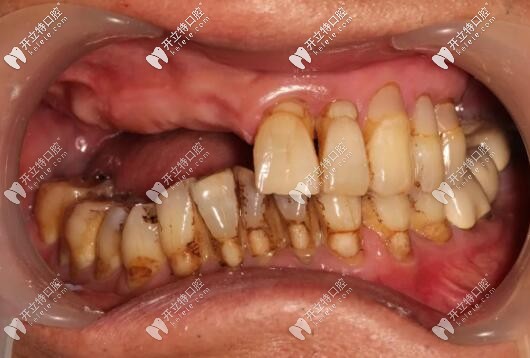

目前已完成ALL-ON-4即刻負(fù)重,通過(guò)手術(shù)情況來(lái)看,效果確實(shí)比較好,作為一位地道老陜?nèi)?,惠先生的感激之情溢于言表?/p>

西安美奧口腔即刻種植牙案例

西安美奧口腔半口種植牙案例

修復(fù)后